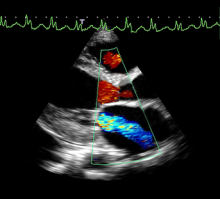

Enhanced features on the Philips EPIQ CVx ultrasound system provide a next level photorealistic 3D rendering, making it easy for users to interpret what they are seeing. The TrueVue feature enhances the sense of depth and space, producing images that appear natural and realistic to the human eye. Â

Watch the video to check out how TrueVue can help improve views of LAA and MV morphology.Â